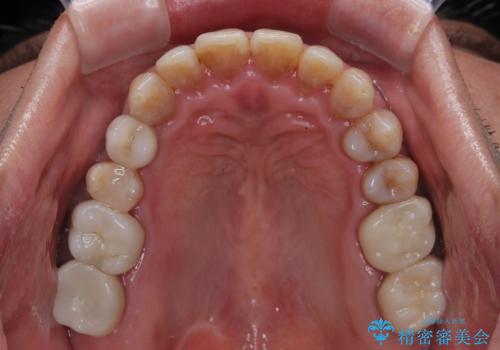

- 前歯のクロスバイトを気にして来院された患者様です。

40代男性で、インプラント補綴治療も経験されている方で、矯正治療をしても良いのかと悩んでいらっしゃいました。

下顎骨の左右のずれがあり、下顎全体が前方に出ている状態であったので、無理をせずにワイヤー装置にて矯正治療を行うこととしました。

クロスバイト改善には難儀しましたが、咬みやすく、笑ったときに清潔感ある口元に仕上げることができました。